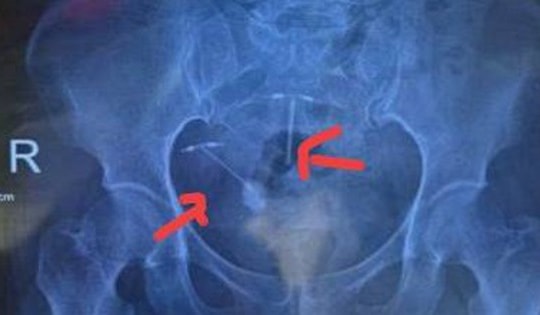

Vòng tránh thai xuyên vào bàng quang, tạo sỏi lớn

Các bác sĩ vừa phẫu thuật nội soi thành công lấy ra vòng tránh thai bị lạc chỗ xuyên vào bàng quang và hình thành sỏi lớn. Đây là biến chứng hiếm gặp nhưng có thể gây hậu quả nghiêm trọng nếu không được phát hiện, xử lý kịp thời.